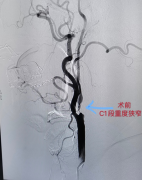

新技術(shù)——菏澤醫(yī)專附屬醫(yī)院首次成功開(kāi)展頸內(nèi)動(dòng)脈支架成形術(shù)

2020年9月25日,菏澤醫(yī)專附屬醫(yī)院神經(jīng)內(nèi)科、介入中心成功為一名重度頸內(nèi)動(dòng)脈狹窄患者實(shí)施了頸內(nèi)動(dòng)脈支架植入術(shù),標(biāo)志著我...